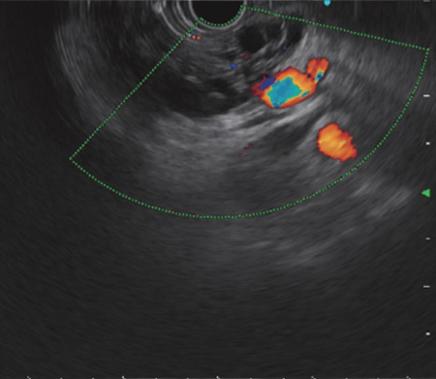

超声内镜(EUS):即内镜和超声相结合的消化道检查技术,将微型高频超声探头安置在内镜顶端,当内镜插入体腔后,在内镜直接观察消化道黏膜病变的同时,可利用内镜下的超声行实时扫描,可以获得胃肠道的层次结构的组织学特征及周围邻近脏器的超声图像,从而进一步提高内镜和超声的诊断水平。

简单来说,医生在使用超声内镜进行检查时,发现病灶,可直接诊断病变的起源层次,并可根据大小、回声特点等初步判定肿瘤性质,是生理性改变还是病理性改变,是器质性改变还是功能性改变等等。

电子凸阵扫描

电子环形扫描

PowerFlow模式

ColorFlow模式

H-Flow模式超声内镜的展望

随着超声内镜技术在临床的普及,其应用越来越广泛,尤其对于消化道肿瘤的术前分期,明确消化道早癌的浸润深度,合理把握内镜下微创治疗的适应症起到重要作用。有了超声内镜这一有利武器,使得许多疑难复杂的消化系统疾病的诊断和治疗变得容易,从而使市中心医院对消化系统疾病的诊治迈上了一个新台阶。